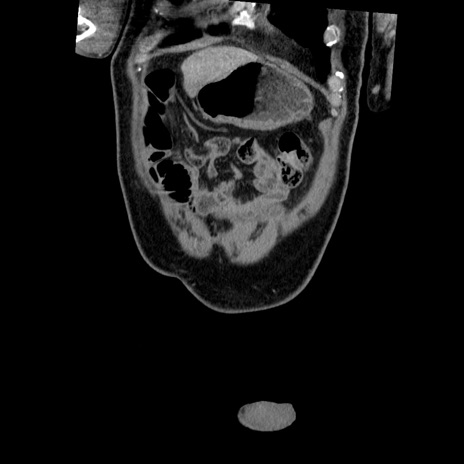

横断像

【症例】50歳代男性

【主訴】腹痛

【現病歴】AVMからの被殻出血のため回復期リハ病棟入院中。 本日午後3時頃急に下腹部痛が出現した。

【既往歴】AVM、被殻出血、虫垂炎、高血圧

【身体所見】意識晴明、左半身不全麻痺、会話の理解は良好、36.5°C、腹部:膨隆、全体に板状硬、下腹部正中に圧痛点あり、反跳痛-、筋性防御不明、右下腹部にope scar

【データ】WBC 9400、CRP 0.06